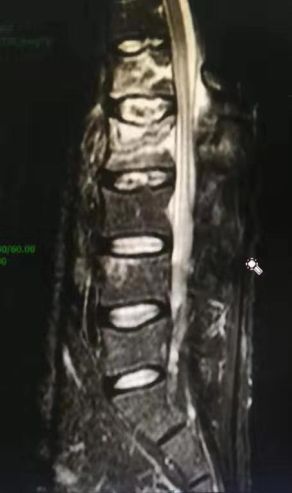

深圳市中医院骨三科的何升华主任经过仔细的检查、看片以后得出诊断结论:病人为强直性脊柱炎合并L1、L2椎体爆裂骨折。

腰椎MRI及CT显示腰1 腰2椎体新鲜压缩骨折

深圳市中医院骨三科的何主任考虑到患者年轻并且合并强直性脊柱炎,椎体多发硬化,不宜采取传统开放性手术。

经过骨科的术前讨论,征求了家人的同意,何升华主任制定了经皮椎弓根螺钉内固定联合过伸体位下弹性按压手法复位的中西医结合的微创治疗方案。